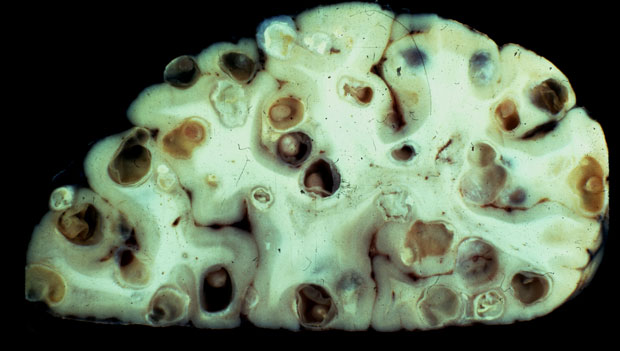

Αυτή η φωτογραφία δείχνει τα αποτελέσματα του Taenia Solium, που όπως και το Spirometra Erinaceieuropaei, κατοικεί σε μυς των γουρουνιών.

Ειδικοί υπολογίζουν πως περίπου 5 εκατομμύρια άνθρωποι σε όλο τον πλανήτη έχουν προσβληθεί από παράσιτα στον εγκέφαλο.